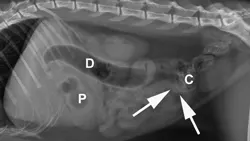

A) Right radiograph, B) Left radiograph, and C) Ventrodorsal radiograph

Radiographic Findings: The stomach (St) and duodenum (D) are severely distended with fluid and gas, suggesting intestinal obstruction or possibly pancreatitis with secondary ileus.

There is a 1.5-cm rounded opaque structure (arrows) in the caudal abdomen, to the left of the descending colon on the VD view. It is partially obscured by feces in the colon (C) on the left lateral view. The remaining organs and serosal detail appear normal.

Comments: We often perform left and right lateral radiographic views of the abdomen in cases of suspected GI foreign bodies and obstructions since the fluid and gas disperse into different portions of the GI tract. For example, any gas in the stomach rises to the pylorus (P) in left lateral recumbency and may outline a foreign body anchored to this region; this is particularly useful in suspected linear foreign bodies, which typically anchor to the tongue or pylorus and subsequently plicate varying degrees of small intestine.